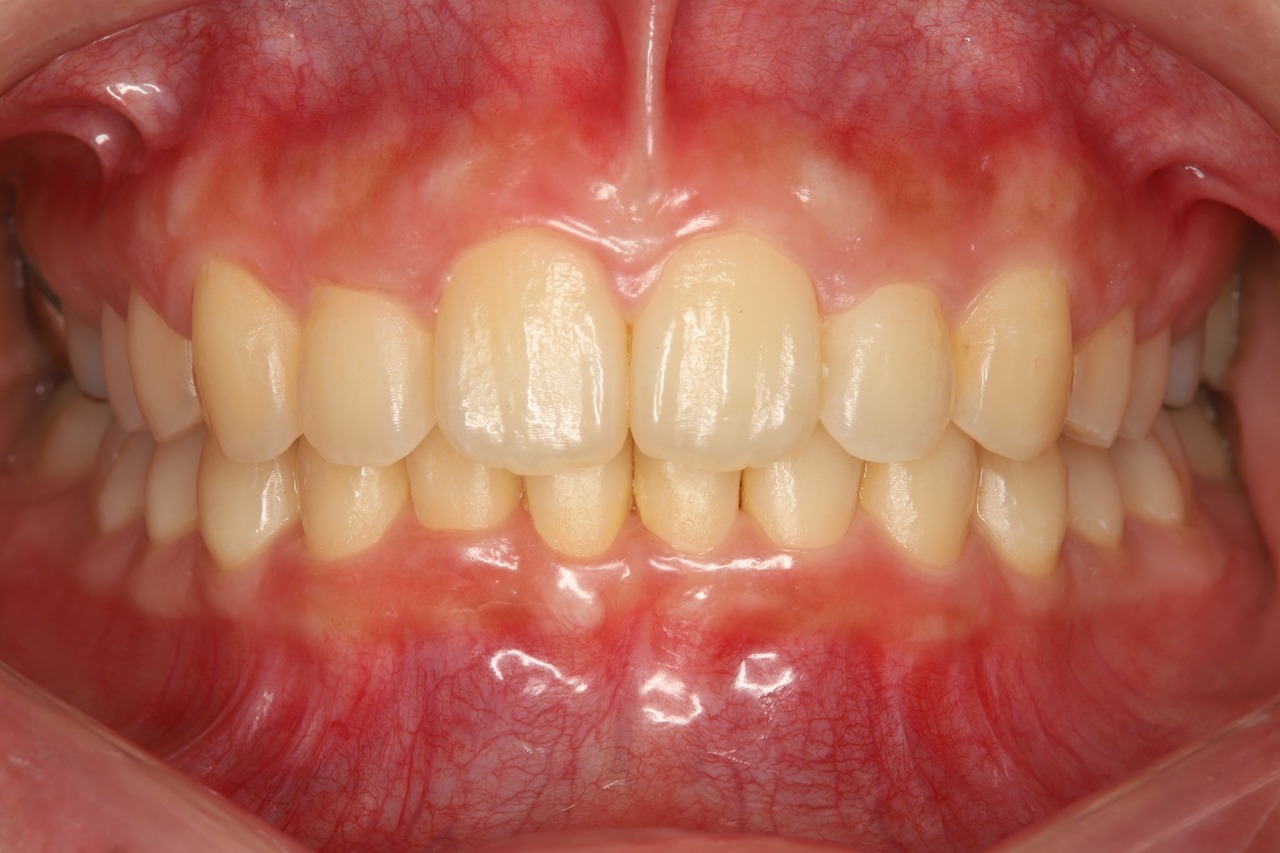

当院でのインビザライン治療例

こちらは当院でマウスピース矯正を行った患者さまです。前歯だけでなく奥歯の咬み合わせまで含めて調整することで、将来的な歯の健康や歯並びの安定を守ります。

Before

After

出っ歯が治り、歯と歯の間に隙間もありません。

奥歯がしっかりと噛み合い、安定した咬み合わせになっています。